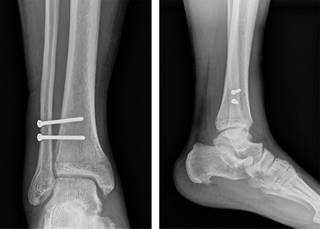

Se realizó un seguimiento de los casos quirúrgicos con lesión y/o fractura de tobillo del servicio de miembro pélvico durante el lapso de un año, se encontraron sólo cuatro casos con una lesión de la sindesmosis tibioperonea distal sin fractura, la cual fue demostrada con radiografía comparativa, exploración clínica y corroborada durante el transquirúrgico. El mecanismo de lesión en todos los casos correspondió a una rotación externa del pie sobre la pierna. El manejo inicial en todos los casos fue inmovilización, después se efectuó cierre quirúrgico de la sindesmosis con doble tornillo situacional de 3.5 mm (Figura 4) y se instruyó diferir el apoyo. Los implantes fueron retirados en un plazo de seis semanas y se inició la marcha en casa. Posterior a los seis meses se realizó un seguimiento a los casos y se aplicó el CAIT.